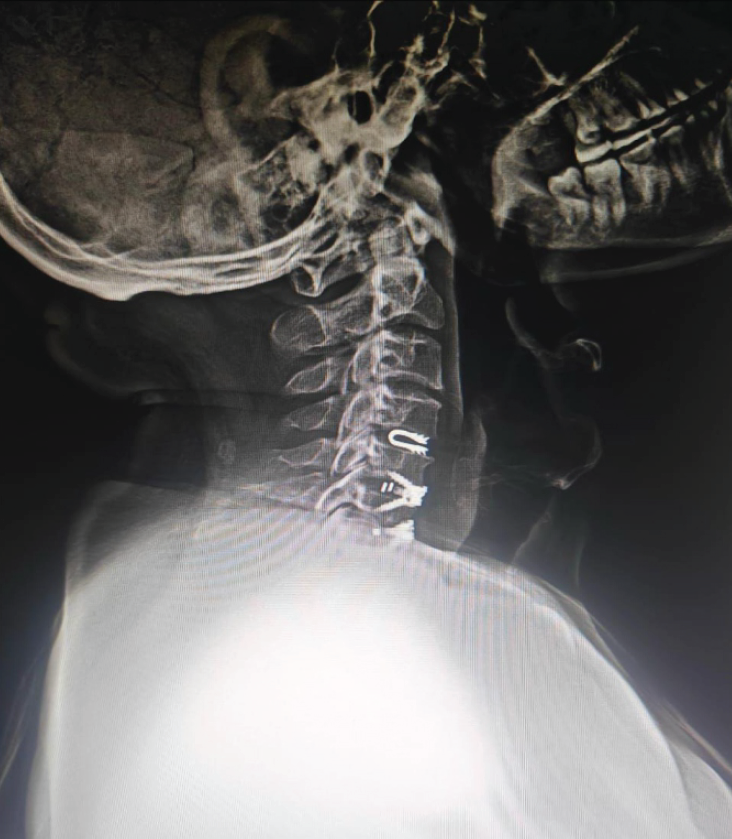

Cervical disc replacement

It has gained traction in the past few years as an alternative to anterior cervical discectomy and fusion in cervical degenerative disc disease. It preserves motion at the operative level, potentially reducing the risk of adjacent segment disease. However, concerns regarding heterotopic ossification, subsidence, and osteolysis remain (Fig. 8).

Figure 8: Lateral cervical spine radiograph demonstrating a dynamic cervical implant at C4-5 level (blue arrow) above the two level anterior cervical discectomy and fusion done at C5-6 and C6-7 levels.

Dynamic cervical implant

It is a U-shaped titanium one-piece non-fusion device – a novel treatment approach to cervical degenerative disc disease. It is designed to work as a shock-absorbing device that protects adjacent segments (Fig. 8).